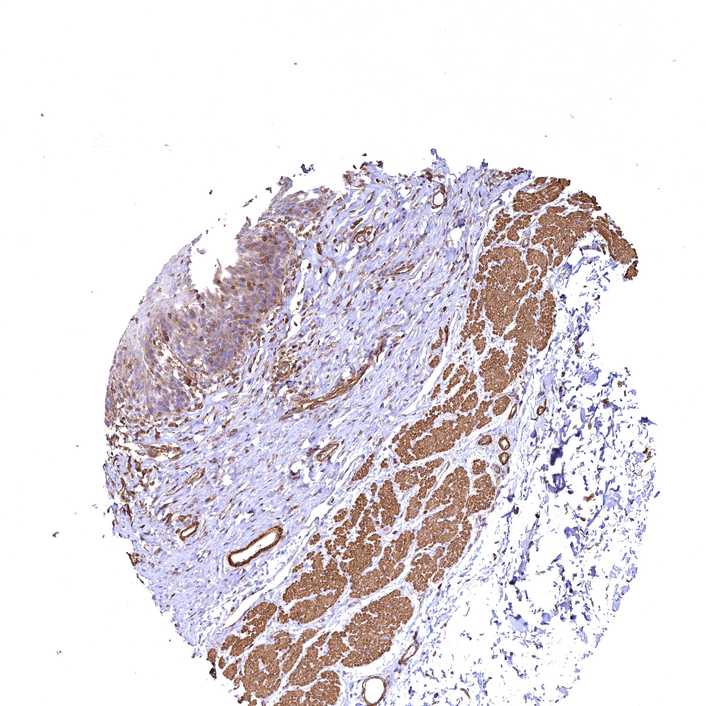

ESOPHAGUS - Antibody stainingi

Antibody staining in the annotated cell types in the current human tissue is reported as not detected, low, medium, or high, based on conventional immunohistochemistry profiling in selected tissues. This score is based on the combination of the staining intensity and fraction of stained cells.

Each image is clickable and will lead to virtual microscopy that enables deeper exploration of all samples and also displays staining intensity scores, fraction scores and subcellular localization as well as patient and tissue information for each sample.

Antibody CAB033678

Squamous epithelial cells Low